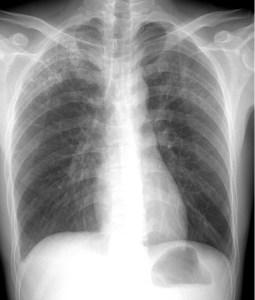

When you get routine X-rays of your teeth at the dentist’s office or a chest X-ray to determine if you have pneumonia, you expect the technologist to drape your pelvis in a heavy radioprotective apron. But that may not happen the next time you get X-rays.

Shielding testes and ovaries during X-ray imaging has been standard practice since the 1950s due to a fear of hereditary risks — namely, that the radiation would mutate germ cells and these mutations would be passed on to future generations. This concern was prompted by the genetic effects observed in studies of irradiated fruit flies. However, such hereditary effects have not been observed in humans.